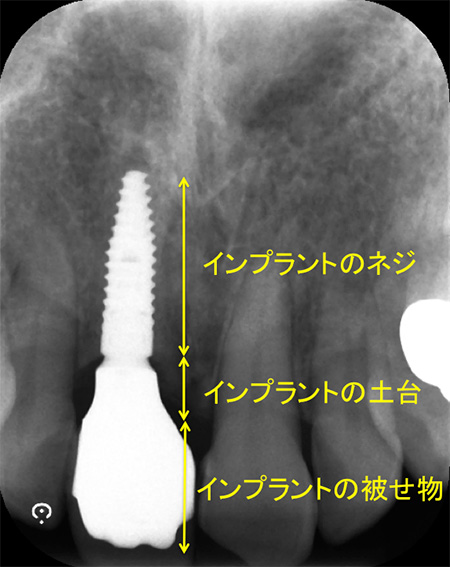

インプラントは3つのパーツから構成されます。

このインプラントの土台部分の形は、インプラントのネジの位置により大きく制限を受けます。

このX線写真のようにネジの位置が適切であれば、土台の移行部がなだらかで磨きやすい形と言えますが、このネジの位置が浅かったり、土台に急な角度がついてしまうとご自身でのブラッシングが困難になります。